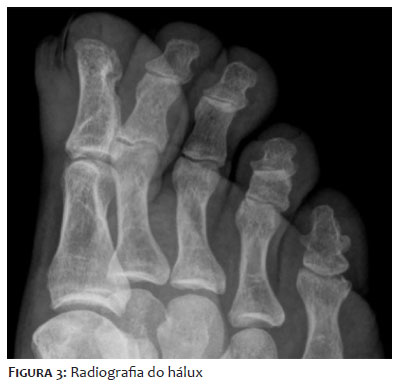

Paciente de sexo masculino, de 48 anos de idade, leucoderma, assistente de informática, compareceu ao serviço de Dermatologia se queixando de alteração da espessura e coloração da unha do hálux direito iniciadas há cerca de 15 anos, acompanhada por dor intensa há 1 ano, com piora progressiva e prejuízo da deambulação. Já havia realizado diversos tratamentos prévios para onicomicose com terbinafina oral e antifúngicos tópicos em outro serviço, sem melhora. Relatou episódios de agudização da dor com drenagem de secreção purulenta periungueal com necessidade de antibioticoterapia sistêmica em diversas ocasiões, além do uso frequente de anti-inflamatórios não esteroidais para alívio da dor. Ao exame dermatológico, o hálux direito apresentava lâmina ungueal espessada e amarelada, com faixa bem delimitada de hiperceratose e hipercurvatura transversa contendo projeções digitiformes e focos de hemorragia em estilhaço, melhor evidenciados à dermatoscopia. Havia também edema e calor da dobra ungueal proximal (Figuras 1 e 2). O exame micológico direto do leito ungueal apresentou resultado negativo, porém na cultura houve crescimento de Trichophyton mentagrophytes. Em radiografia de hálux direito (Figura 3), houve dúvida quanto à presença de lesão falangeana distal em saca-bocado em área subjacente à lesão ungueal. Foi solicitada ressonância magnética de hálux direito (Figuras 4 e 5), que evidenciou lesão ovalada em matriz, com hipossinal em T1 e sinal heterogêneo em T2, de limites imprecisos sem infiltração de partes moles, porém ocasionando remodelamento do contorno ósseo. Optou-se por abordagem cirúrgica com biópsia excisional de lesão para confirmação diagnóstica, sendo realizado bloqueio anestésico distal, descolamento da lâmina ungueal e exérese de lesão exofítica medindo 1,5 cm por 0,5 cm em matriz ungueal. No peroperatório foi evidenciada a presença de projeções digitiformes da placa ungueal em direção à lesão da matriz (Figura 6). A análise histopatológica, com coloração de hematoxilina eosina, evidenciou lâmina ungueal com cavitações preenchidas por plasma e tumor fibroepitelial com projeções digitiformes do epitélio matricial e alguns mastócitos de permeio, compatível com o diagnóstico de OM (Figuras 7 A, B).

A clínica é caracterizada por uma porção bem demarcada da placa ungueal com evidente espessamento, presença de hemorragia em estilhaço, hipercurvatura transversa e xantoníquia, sendo esta o sinal mais comum, observado em pouco mais de 50% dos casos.2 Outras características incluem: eritema e edema da prega ungueal proximal, sulco longitudinal proeminente, melanoníquia longitudinal, onicodistrofia e pterígio dorsal.2,9 Pode ou não haver dor associada. O achado de projeções digitiformes é bastante sugestivo após a avulsão cirúrgica da lâmina ungueal.5 Os diagnósticos diferenciais principais são o fibroqueratoma e o fibroma periungueal, mas também incluem carcinoma de células escamosas, doença de Bowen, verruga vulgar subungueal, queratoacantoma, osteocondroma e infecções fúngicas e bacterianas. Pode apresentar-se também com melanoníquia longitudinal associada, incluindo como diagnóstico diferencial as desordens de proliferação e ativação de melanócitos da matriz ungueal.2 A coexistência de OM e onicomicose é comum, uma vez que as cavitações tornam a placa ungueal mais susceptível a infecções fúngicas secundárias. Casos de OM frequentemente são tratados como onicomicose, levando ao atraso do diagnóstico e uso desnecessário de medicações sem resposta.10,11 Portanto, o achado de hifas hialinas septadas ao exame micológico direto ou o crescimento fúngico em cultura não excluem o diagnóstico de OM, e a ausência de resposta à terapia padrão deve sugerir a hipótese de outros diagnósticos diferenciais.4 Na dermatoscopia há espessamento da placa ungueal com múltiplas cavitações semelhantes a favo de mel (70%), estrias hemorrágicas (72%) e sulcos longitudinais brancos que correspondem aos canais da placa ungueal (71%). As cavitações em favo de mel podem ser preenchidas por material de pigmentação amarelada ou vermelha a preta. Enquanto os padrões de espessamento da placa e hemorragia em estilhaço não apresentam grande especificidade, podendo estar presentes em casos de onicomicose isoladas, a presença de sulcos brancos longitudinais paralelos associados à demarcação lateral da lesão e cavitações em favo de mel possui grande especificidade.2,4,5,7,12 Podem ser solicitados exames complementares para excluir acometimento ósseo e explorar a presença do OM, porém tais exames não são necessários para confirmação diagnóstica. A ultrassonografia tem maior valor preditivo quando realizada por profissional experiente e pode evidenciar áreas hipoecogênicas na matriz ungueal com áreas lineares hiperecogênicas adjacentes, que correspondem às projeções digitiformes.5,11 A radiografia do dígito acometido é um exame de fácil acesso e pode excluir acometimento ósseo, mas não apresenta sinais típicos para a conclusão diagnóstica. A ressonância magnética, apesar de não ser necessária de rotina, evidencia hipocaptação de sinal em lesão e em matriz ungueal e hipercaptação de sinal adjacente correspondendo às projeções tumorais.3,5 No caso apresentado, a radiografia apresentava imagem duvidosa em falange distal do hálux direito, que poderia corresponder ao acometimento ósseo -(lesão em saca bocado), então optou-se por um segundo exame de imagem antes da abordagem cirúrgica para melhor planejamento. Na histologia, os OM são tumores fibroepiteliais compostos por duas porções distintas. A zona proximal é caracterizada por invaginações epiteliais profundas ocupadas por saliências ungueais. A zona distal abrange as digitações epiteliais originárias do epitélio da matriz, que prolifera e causa perfurações na lâmina ungueal.2,13,14 A imuno-histoquímica é de grande auxílio diagnóstico, com positividade para CD34 e negatividade para marcadores CD99, proteína S-100, antígeno epitelial de membrana, actina e desmina.1 A suspeição clínica somada a exames complementares como radiografia, ultrassonografia, ressonância magnética e dermatoscopia tem grande valor, mas o diagnóstico só pode ser confirmado após análise histopatológica.5,7 O tratamento consiste na excisão cirúrgica completa do tumor, incluindo a matriz ungueal normal proximal à lesão para prevenir recidiva local. Apesar de se tratar de um tumor benigno, recomenda-se seguimento a longo prazo devido ao risco de recidiva. Não raramente complica com distrofia ungueal permanente.2,15 Apesar de apresentar características clínicas e intraoperatórias clássicas, a falta de conhecimento sobre essa doença e sua tendência a ser assintomática contribuem para um diagnóstico tardio. Diante de um caso de aparente onicomicose intratável associada à hipercurvatura transversa, espessamento ungueal e hemorragias em estilhaço, deve-se suspeitar de OM subjacente.